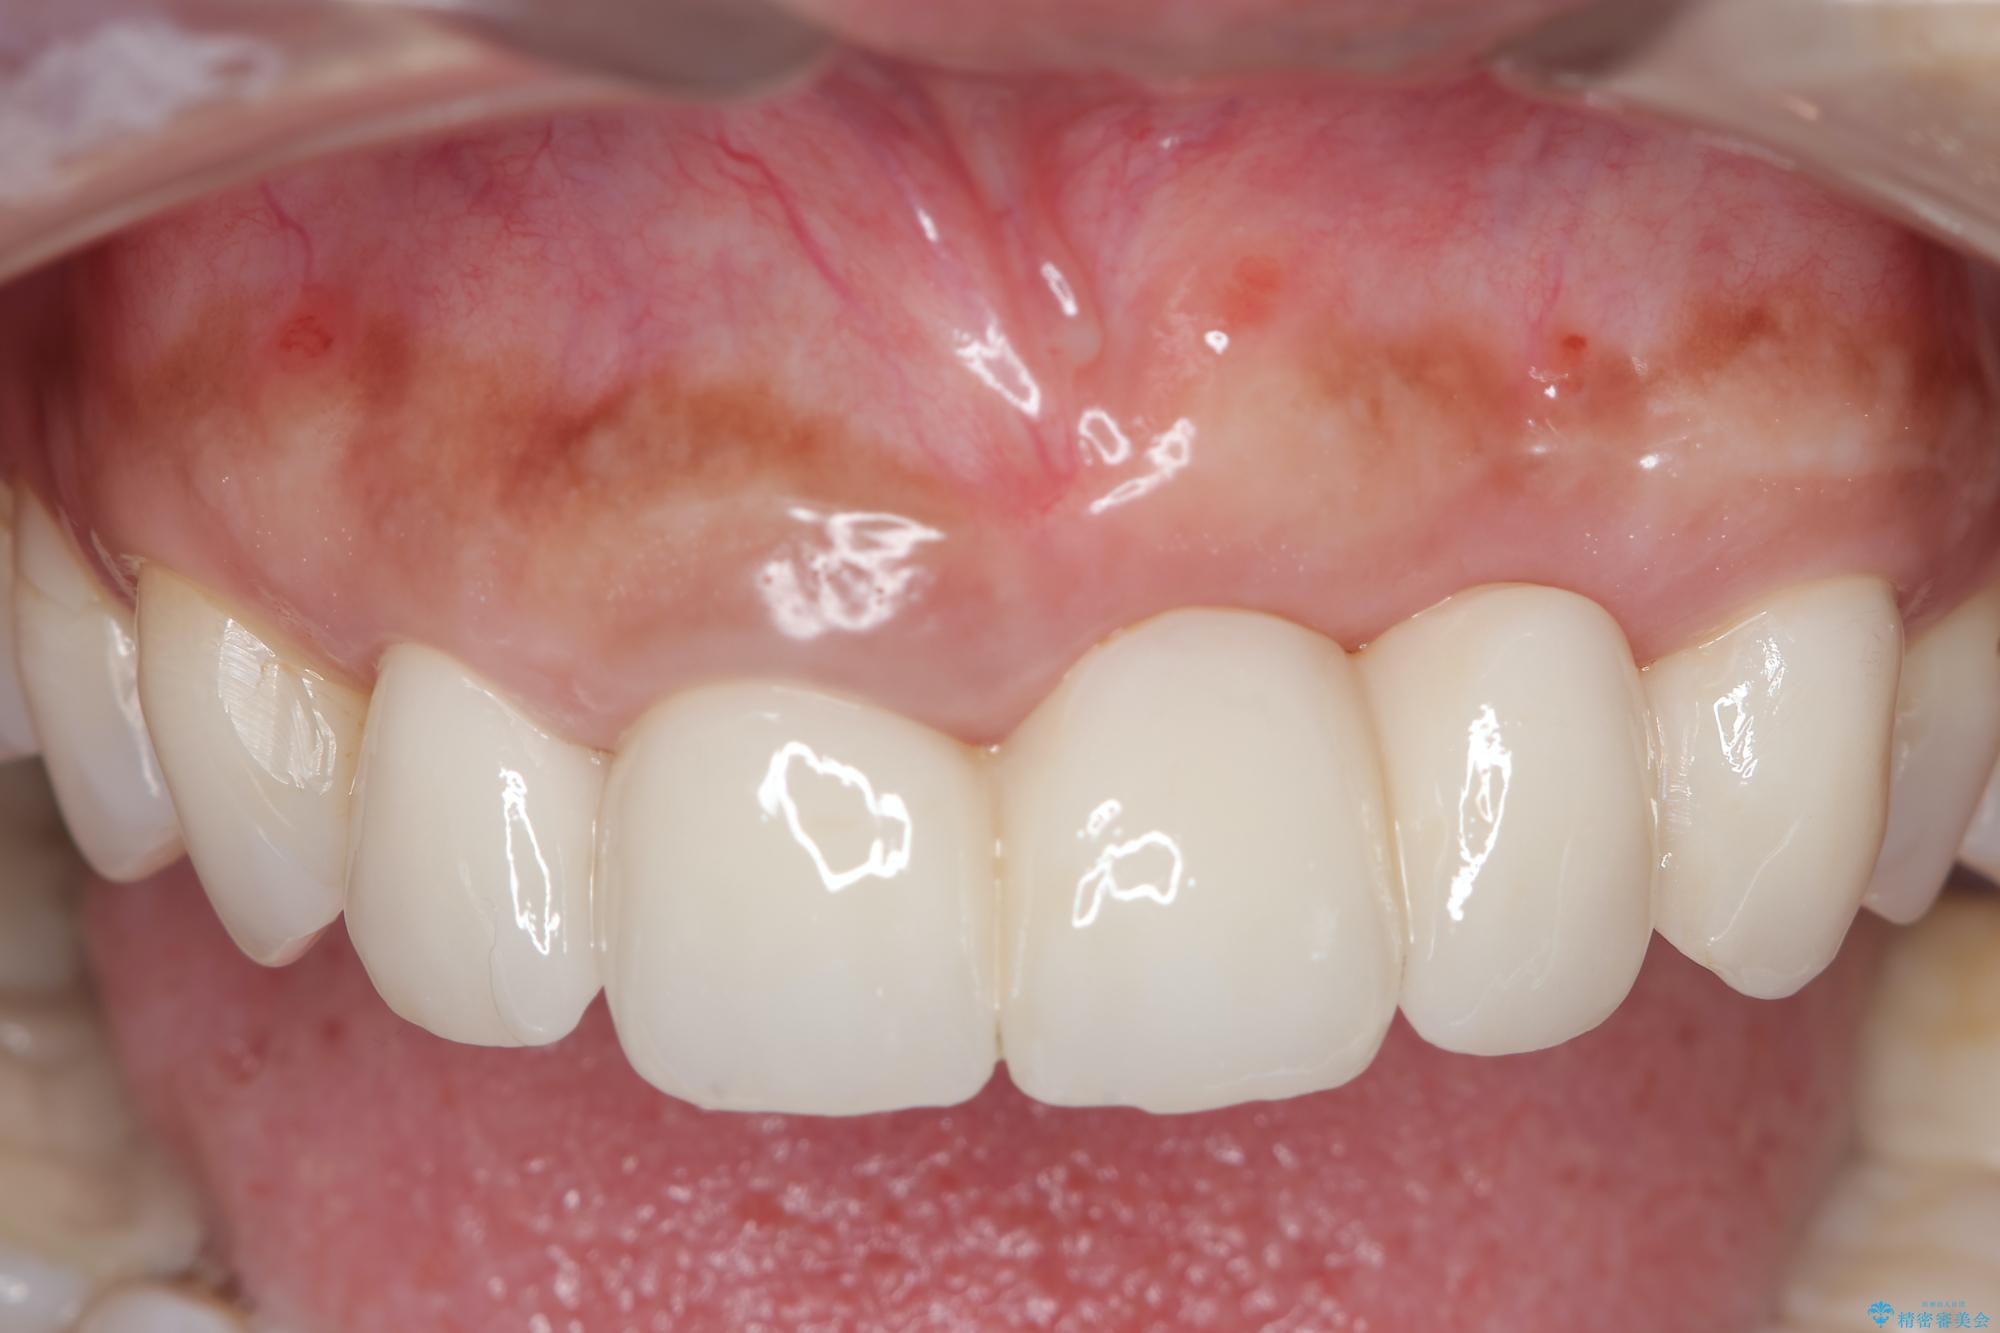

治療を終えて

一件綺麗に見えるセラミックも適合や精度が悪いと、内部で虫歯が進行し亀裂や破折、悪臭の原因となることがあります。

治療後

歯槽堤保存術を併用したブリッジ治療 治療後画像 歯槽堤保存術を併用したブリッジ治療 治療後画像 歯槽堤保存術を併用したブリッジ治療 治療後画像 歯槽堤保存術を併用したブリッジ治療 治療後画像 歯槽堤保存術を併用したブリッジ治療 治療後画像 歯槽堤保存術を併用したブリッジ治療 治療後画像 歯槽堤保存術を併用したブリッジ治療 治療後画像